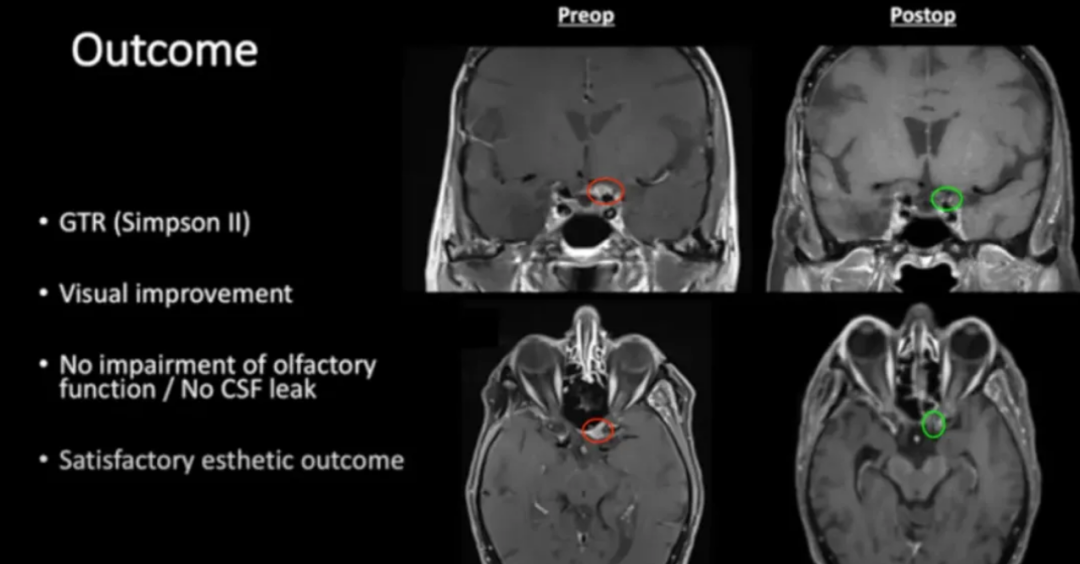

福教授在手术中采用了内镜辅助下右额下入路肿瘤全切术,为她实施了精准的手术治疗。该手术实现了肿瘤的完全切除,达到了辛普森II级标准。术后,患者的视觉功能得到了显著改善,同时嗅觉功能也保持了完好,没有出现脑脊液渗漏的情况。

术前及术后磁共振成像。术前preop(A)和术后Postop(C)显示肿瘤完全切除。